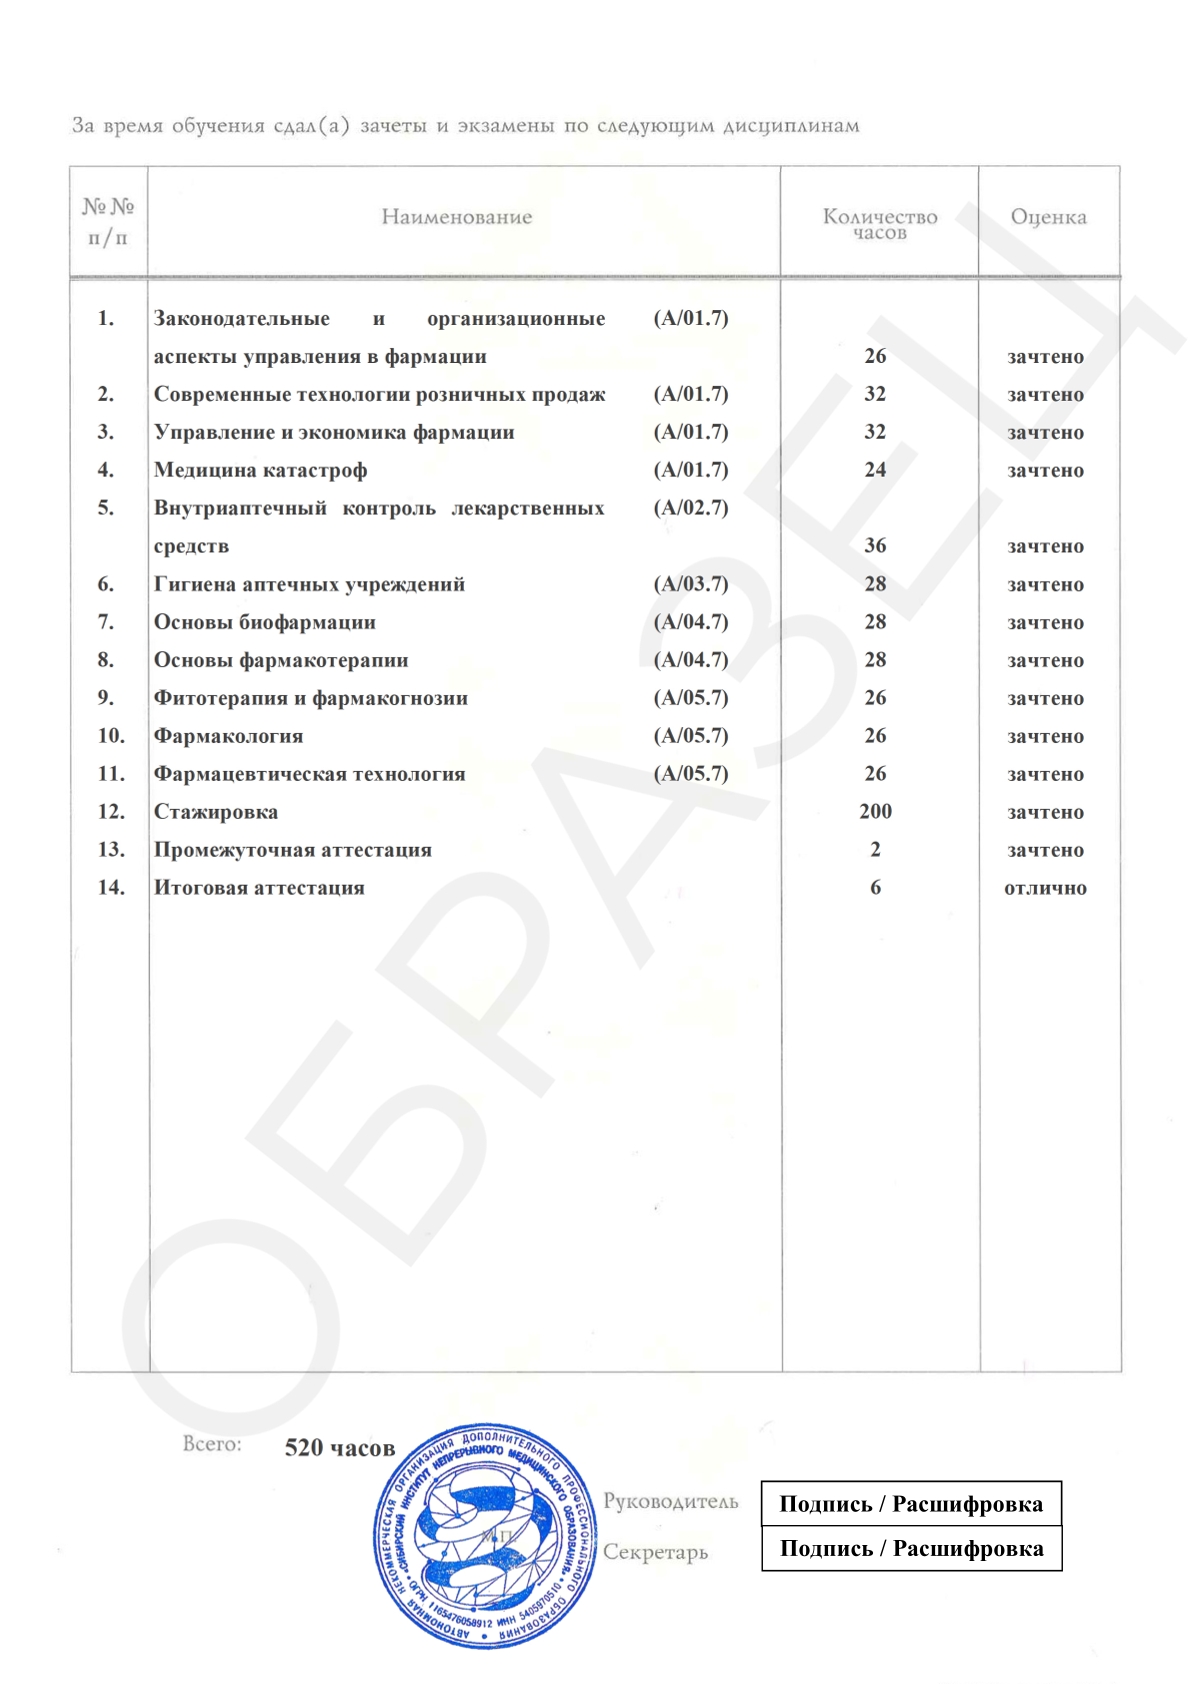

Смотреть документ

Смотреть документ